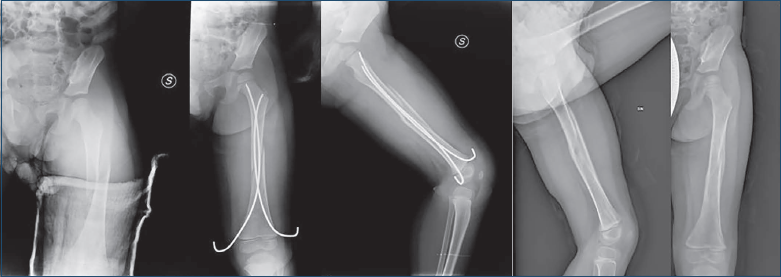

L’uso dei chiodi elastici nel trattamento delle fratture di femore si deve alla Scuola Nancy nel 1979 2: esso ad oggi rappresenta la nostra metodica di scelta nel trattamento di queste fratture nei pazienti sopra i 6 anni di età per la facilità della tecnica operatoria e gli ottimi risultati a distanza.

Tecnica chirurgica di riduzione e sintesi con ESIN

Eseguiamo l’intervento in anestesia generale sotto profilassi antibiotica senza letto di trazione. Ottenuta la riduzione chiusa tramite trazione e rotazione e appena l’allineamento è confermato sui due piani dall’amplificatore di brillanza, eseguiamo inchiodamento retrogrado con due chiodi elastici. Applichiamo due chiodi dello stesso diametro; per la scelta della misura utilizziamo la formula proposta da Kasser and Beaty 23, diametro interno/2-0,5 mm, in modo da ottenere circa il 70-80% di riempimento del canale e ciò ci garantisce una sufficiente stabilità di frattura. Contrariamente a quanto previsto dalla tecnica operatoria, non affondiamo i chiodi elastici nel sottocute, preferendo lasciarli percutanei poiché in passato abbiamo osservato migrazioni nel canale femorale e alcune difficoltà all’estrazione. Questa scelta, sebbene ponga qualche disagio al paziente e lo obblighi ad una maggiore oculatezza nella gestione dei tramiti nel follow-up a lungo termine, non pone grandi problematiche e l’unico reale rischio consiste nell’infezione locale del tramite in misura confrontabile a quanto accade con gli elementi di presa del fissatore esterno. Questa metodica di trattamento riduce i tempi di ospedalizzazione e di conseguenza i costi, risulta ben tollerata dai pazienti, e la facilità della tecnica operatoria lo rende facilmente riproducibile (Fig. 6).

Figura 6. Paziente di anni 7, all’arrivo in PS immobilizzato nella notte in ferula e trattato con chiodi elastici giungendo a consolidazione a 60 gg.